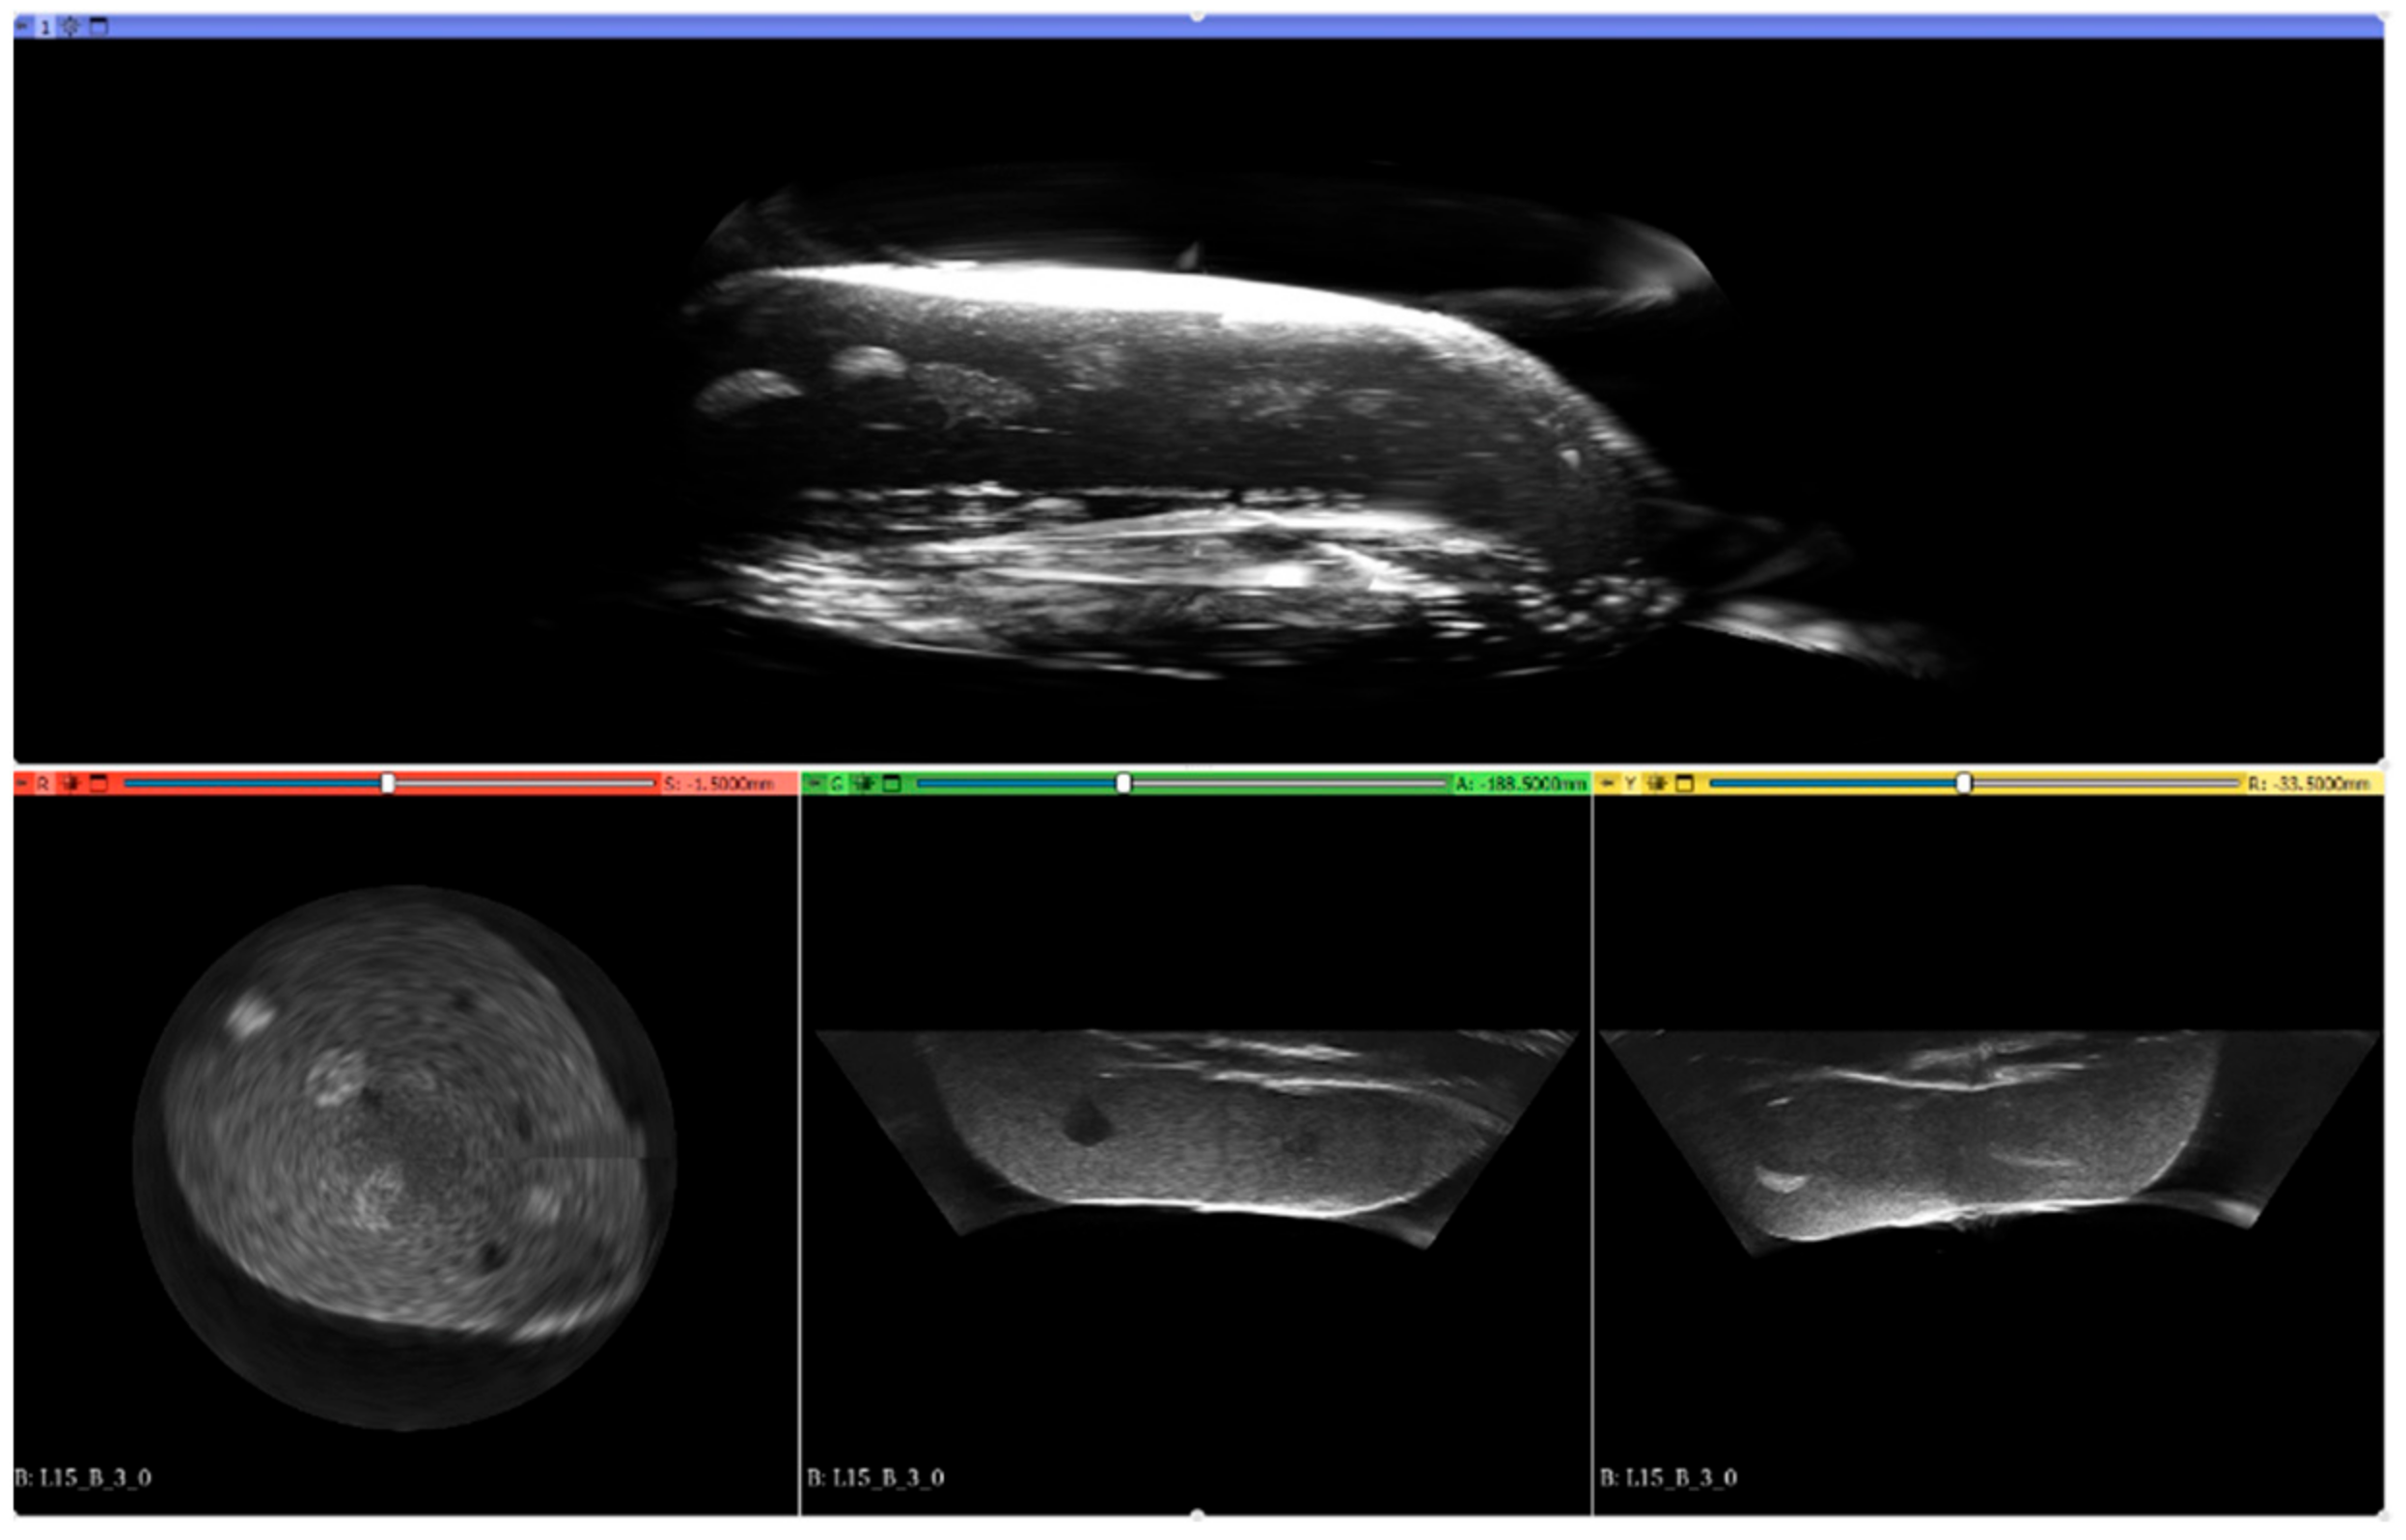

Reconstruction of the 3D image using the MACUI method is a straightforward operation. As the probe is placed radially and rotates around the vertical axis, the polar coordinates of the individual scans can be simply converted to cartesian coordinates. However, a simple concatenation of the opposite images may exhibit artifacts in the center of the image, especially when the sectoral scan is used. In such a situation, the ultrasound beam reaches the structure through different acoustic paths and incidents with it at different angles. The case has been studied by the authors and different compounding methods have been evaluated to minimize unwanted effects [49]. The proposed weighted average method has been used in this work during reconstruction. Having the polar coordinates converted to cartesian, all values can be converted into the stack of images that can be subsequently reconstructed using software, such as 3D Slicer, or converted to DICOM format and evaluated by any software that supports DICOM, i.e., Onis Viewer. The 3D Slicer has been used to present the results. Figure 7 presents an example 3D view of the reconstructed structure from the data collected for this study.

Figure 7.

Example 3D reconstruction of the imaged structure of Blue Phantom Breast Masses.